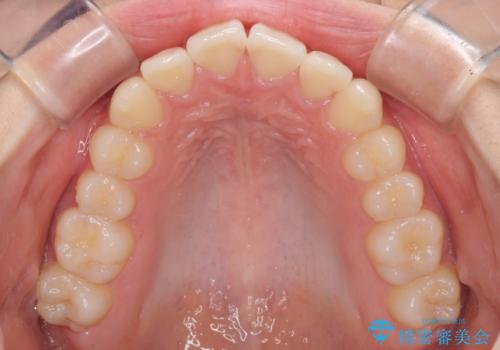

ゴムかけをしっかりと行ってもらい、スッキリとした口元に仕上げることができました。